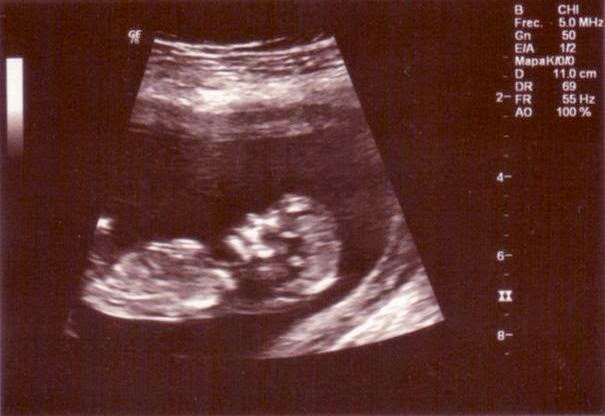

Todavía falta mucho tiempo para que nazca el bebé, ahora estoy de 12 semanitas, pero desde el primero momento que lo hemos dicho a los peques y están disfrutándolo muchísimo! Saben que vendrá para un poquito antes de navidades, así que esto nos ya tenemos tarea con la cuenta atrás!

De momento, os enseñamos esta preciosa foto de nuestro pequeñin a las 12 semanas que desde aquí os saluda a los seguidores de Creciendo Con Montessori: